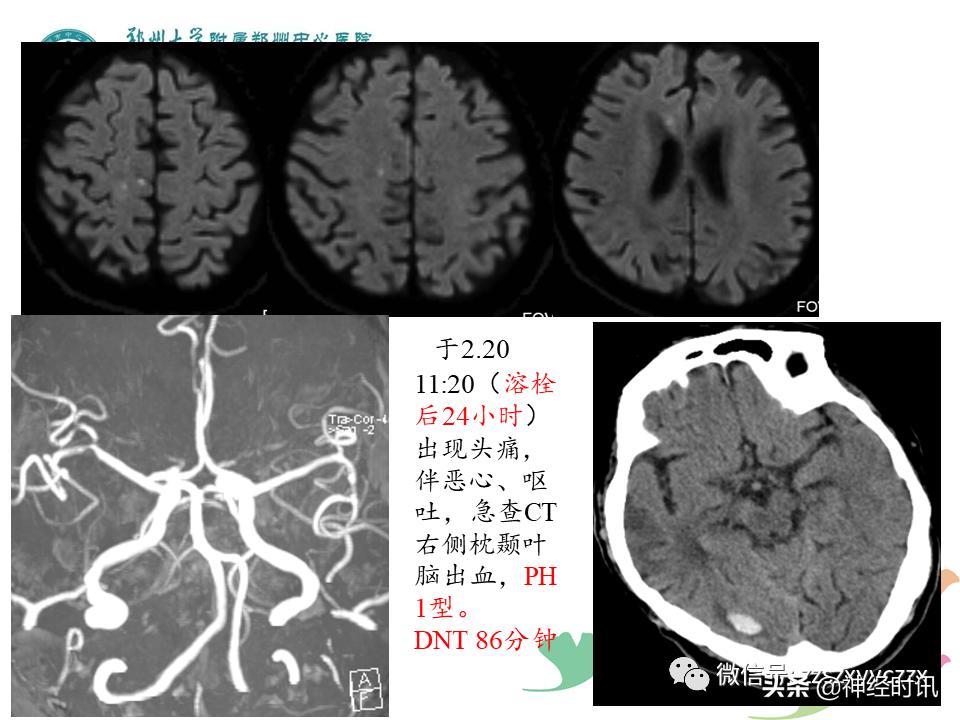

溶栓后脑水肿一般出现在溶栓后24-48小时内,可表现为高颅压症状(头痛、呕吐、视乳头水肿),神经功能恶化,意识状态改变,脑水肿严重者可能发生脑疝。溶栓后脑水肿的发生发展可能与患者溶栓前较高的NIHSS评分、高密度脑动脉征、早期梗死征象的存.在以及治疗延迟有关。

溶栓后脑水肿的处理措施包括床头抬高30°,使用脱

水药和激素等,外科去骨瓣减压以及改善患者全身状V态。